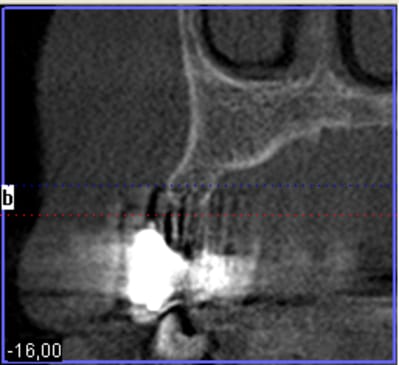

pour débuter ce post je propose un petit cas avec une ROG un comblement alvéolaire et un lambeau pédiculé pour fermer le site d'extraction.